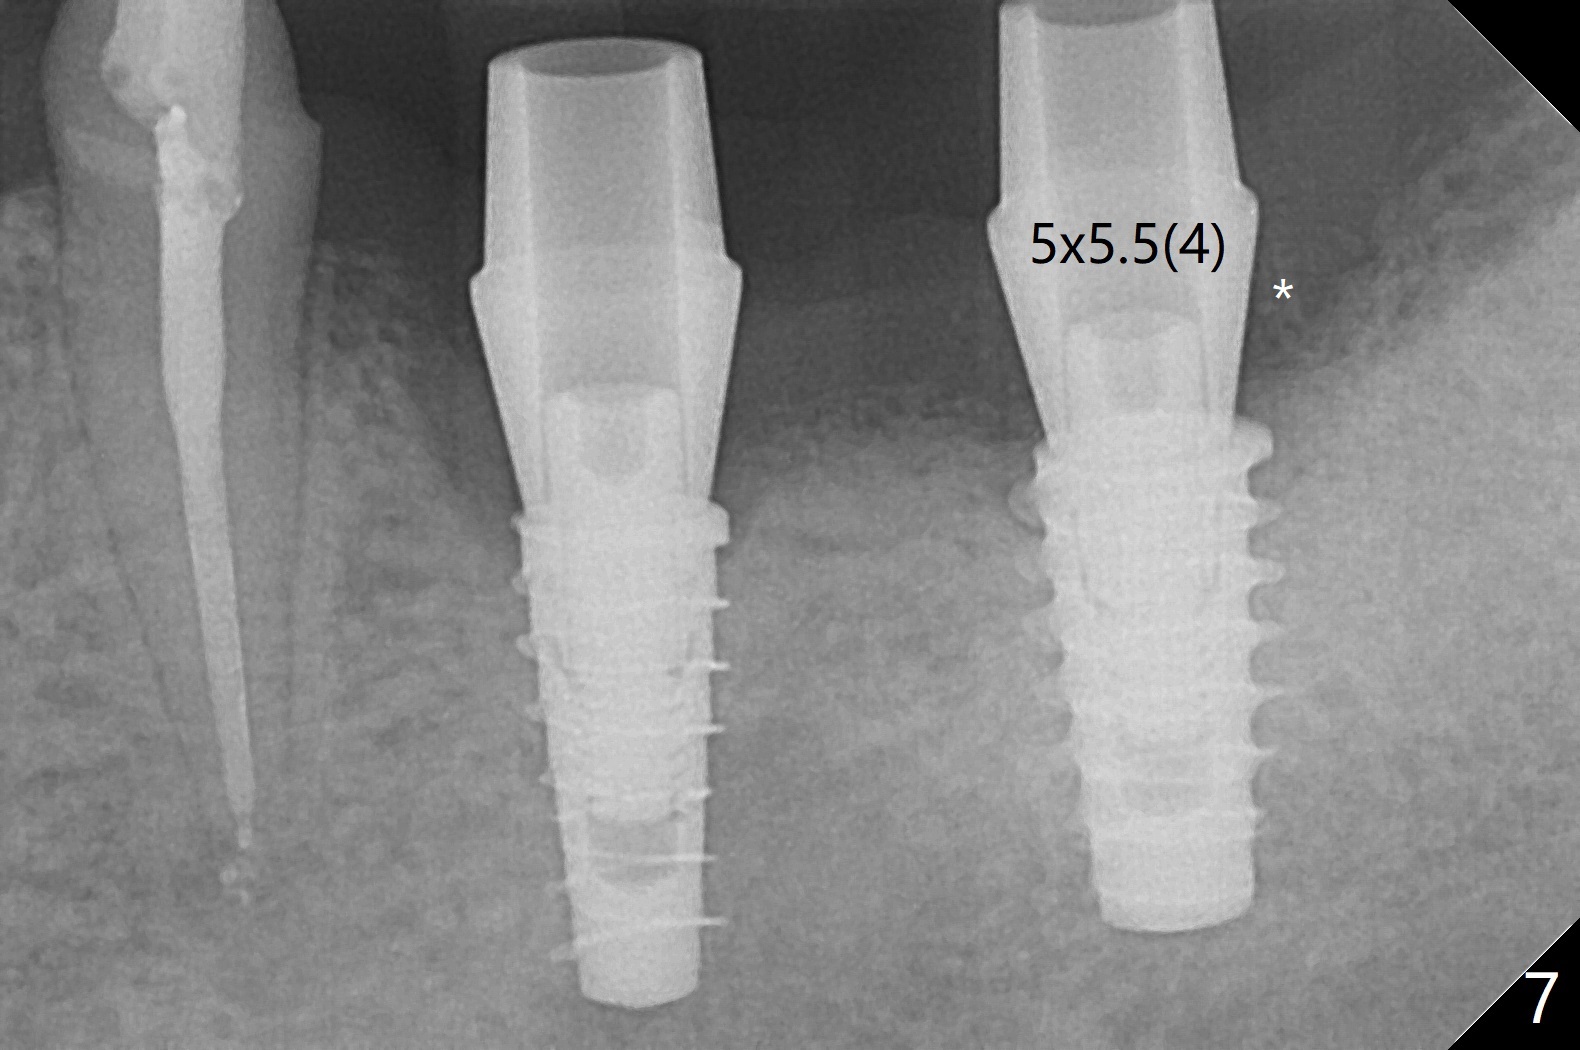

The female woman is afraid of pain. After placement of 4x9 mm FC implant at #19, infiltration anesthesia is not enough for osteotomy at #18. Block anesthesia is added. When a 5x9 mm FC implant is placed in the osteotomy (designed for 5x8.5 mm IS one), it is close to the Inferior Alveolar Canal (Fig.1 red dashed line; Fig.2 (*: bone graft with PRF)). The third contributing factor is the pressure upon the distal end of the distal end guide while osteotomy. A few hours later, the patient reports no paresthesia. The implant placement level and trajectory are normal at #18 and 19 (Fig.3-5). To check pair abutment seating with 30 Ncm torque, PA is taken after removal of healing abutments 4 months postop (Fig.6-8). First the cuff of the abutment is short, subgingival distal of #18 (Fig.6 * (gingiva)). When an abutment with longer cuff is placed, it appears to be close to the distal crestal bone (Fig.7 *). Finally a smaller abutment seams to be appropriate (Fig.8). Retrospectively the larger abutment (6.5x4(4) mm) is incompletely seated initially (Fig.1 with gap).